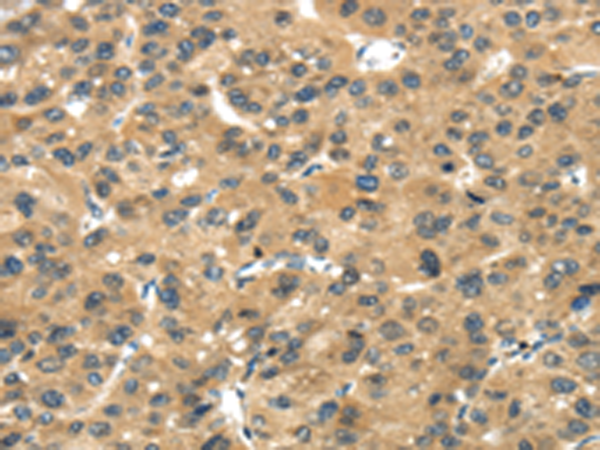

分类: 科研抗体货号: P08887别名: ECRG1应用: IHC反应种属: Human